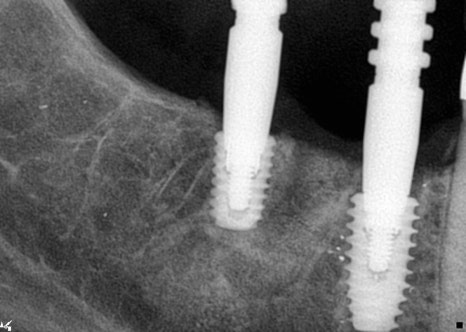

엑스레이 상에 보이는 것처럼 오른쪽 아래

#46 #47번은 힐링으로 지금 되어 있어

잇몸밖으로도 힐링이 보이고

#37은 커버스크류로 되어 잇몸 안에 있어

간혹 환자분들이 식립 후에 입안에서

안보이신다고 하시기도 합니다.

그래서 수술이 끝나고 엑스레이 촬영을 다시 하여

수술 성공 여부와 환자분께 확인시켜드리려

다시 한번 설명드리고 있습니다.